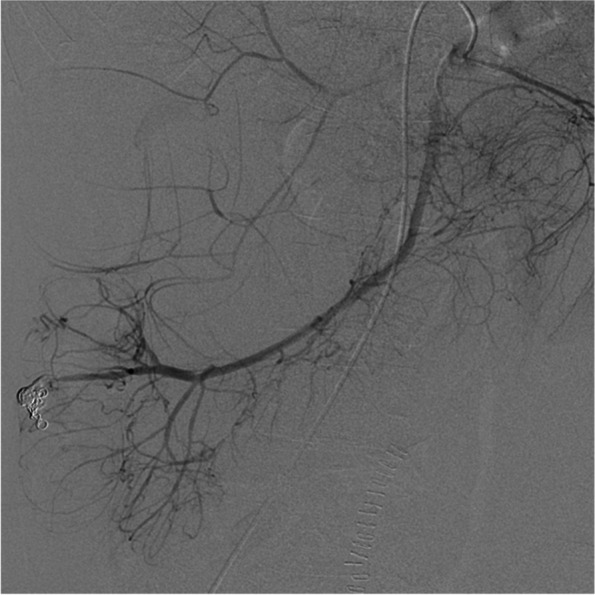

Immediately before entering the operating room, the patient exhibited a decreased level of consciousness, worsening blood pressure, and fetal bradycardia dysrhythmia (heart rate 60 bpm). An emergency cesarean section was then successfully performed (blood loss in the surgical field: 639 mL). The newborn had a birth weight of 2550 g, and the Apgar scores were 1 and 2 at 1 and 5 min, respectively. The patient was transferred to the angiography room under general anesthesia due to persistent hemodynamic instability and hematochezia. A superior mesenteric angiogram revealed an ascending colonic AVM with extravasation of the contrast medium from a branch of the ileocolic artery (Fig. 3A, B).

Fig. 3.

Intraoperative angiography before embolization. A Superior mesenteric artery angiography shows contrast extravasation (arrow) in the distal ileocolic artery. B Selective ileocolic artery angiography with microcatheter revealed contrast extravasation to the ascending colon lumen (arrowhead) and abnormally dilated vessels